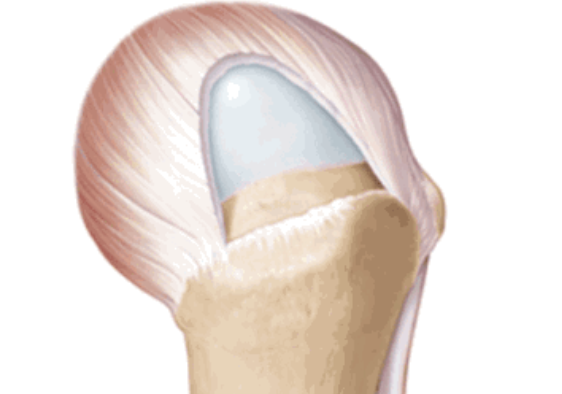

肩袖撕裂分类

按照损伤程度分为部分撕裂( MR准确性>85% )和完全撕裂(MR准确性>95% )。

部分撕裂按照受损部位又分为滑囊面、关节面及肌腱内撕裂,在MRI上可以清晰的看到其受损部位。按照损伤深度分为1级:撕裂深度小于3mm,2级:撕裂深度在3-6mm,3级:撕裂深度大于6mm。

全层撕裂按照范围分为小撕裂:撕裂口<1cm,中撕裂:撕裂口1-3cm,大撕裂:撕裂口3-5cm,巨大撕裂:撕裂口>5cm。高清晰度的MRI是可以测定撕裂范围的。

按照撕裂的形状又分为新月形撕裂、U形撕裂、L形撕裂、倒L形撕裂、巨大回缩性/不可移动性撕裂。想要判断损伤的形状需要在MRI上利用多个平面、多张照片来分析。